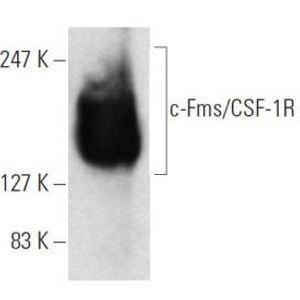

JUL 28, 2025Drug Discovery & DevelopmentOne lab technique that has been around since what feels like the dawn of time is Western blotting, and it doesn&r ...